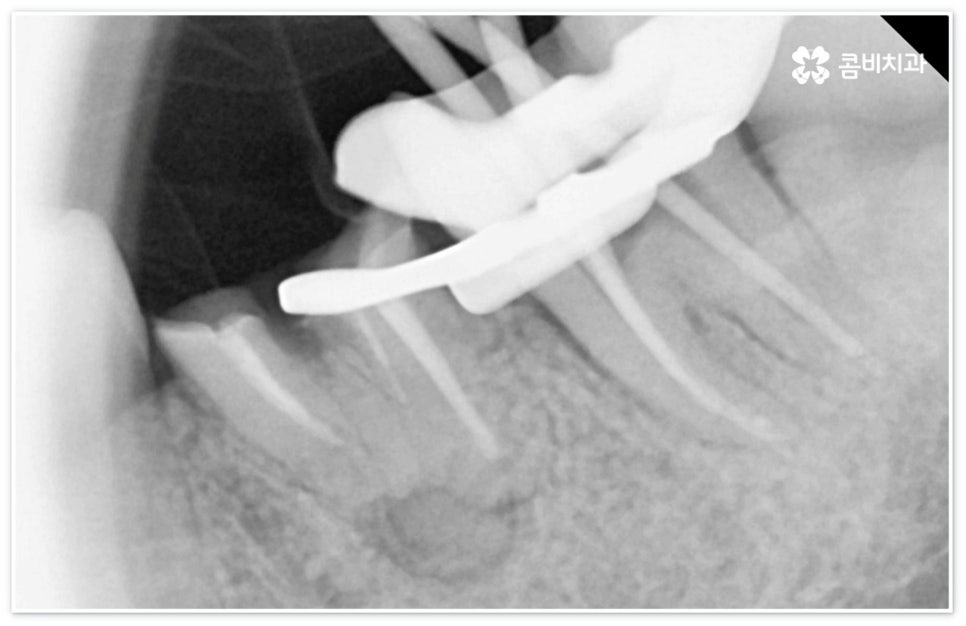

신경치료는 일견 간단해 보일 수 있으나 사람의 신경이 매우 얇고 또한 환자분들마다 신경관의 개수와 모양이 다 다르기 때문에 오염된 부위를 끝까지 깨끗하게 제거하기 위해서는 매우 섬세하고 뛰어난 기술력을 요하므로 다양한 임상 경험을 통해 풍부한 노하우를 가지고 있는 의료진과 함께 하실 필요가 있습니다.

신경치료는 오염된 치수 조직을 제거하여 감염이 더이상 진행되지 않도록 하고 치과용 충전재로 내부를 빈틈없이 채운 후 크라운 보철물을 씌워 남아있는 자연 치아를 쓸 수 있도록 하는 치료이기 때문에 그 과정에서 치아 깊숙한 곳까지 기구로 파고들어 가므로 주변 치아 조직이 예민해지면서 치료 후 며칠에서 길게는 몇 주까지 신경치료통증 을 느끼실 수 있는데요.

혹여 미세한 부근관의 염증을 놓치거나 사후 외부 원인으로 2차 감염이 일어나는 경우 신경치료통증 이 오래 지속될 수 있으니 며칠이 지났음에도 욱신거림이 줄어들기는 커녕 점차 심해진다는 느낌이 있다면 다시 한 번 치과로 내원하셔서 꼼꼼하게 검진 후 필요한 치료를 받으시는 게 좋을 거예요. 상황에 따라 재신경치료를 진행해야 할 수도 있고 좀 더 지켜보면서 발치가 불가피하지는 않은지 신중하게 판단해야 할 수도 있는데요. 예를 들어 만약 신경치료통증 의 원인이 치료 전부터 치아 뿌리에 생겼던 미세한 균열 때문이라면 치료 받은 치아로 씹을 때 통증이 지속적으로 나타날 수 있고 재신경치료 등으로 이를 살릴 수 없으므로 이 통증이 일상생활에 큰 영향을 주지 않을 경우 최대한 사용하는 데까지 사용을 하다가 임플란트 치료를 권장 드리고 있으나 증상이 심할 경우 바로 발치를 해야 하며, 매우 낮은 확률이긴 하지만 신경관 내부 뿐 아니라 외부에도 세균 군집이 생겨 치아 뿌리 끝 염증이 나아지다가 다시 악화된 상황이라면 역시 약 처방 등으로 신경치료통증 을 잡을 수 없고 발치 후 임플란트 식립을 통해 치료해야 할 거예요.